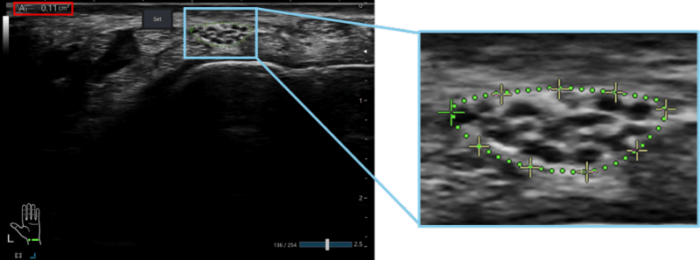

The measurement results are displayed on the screen as the contour of the nerve region and the numerical value of the cross-sectional area, allowing the physician to review them (Fig. 3). After verifying the accuracy of the measurement result, the physician can easily fine-tune the contour by moving the control points displayed on the screen (the crosshair points in the right panel of Fig. 3) via touch operation, as needed. The spacing between control points was designed to be wider than a fingertip to reduce stress during touch operation.

Fig.3 Example display of the automatically measured nerve contour (green dashed line) and the cross-sectional area value (inside the red box)